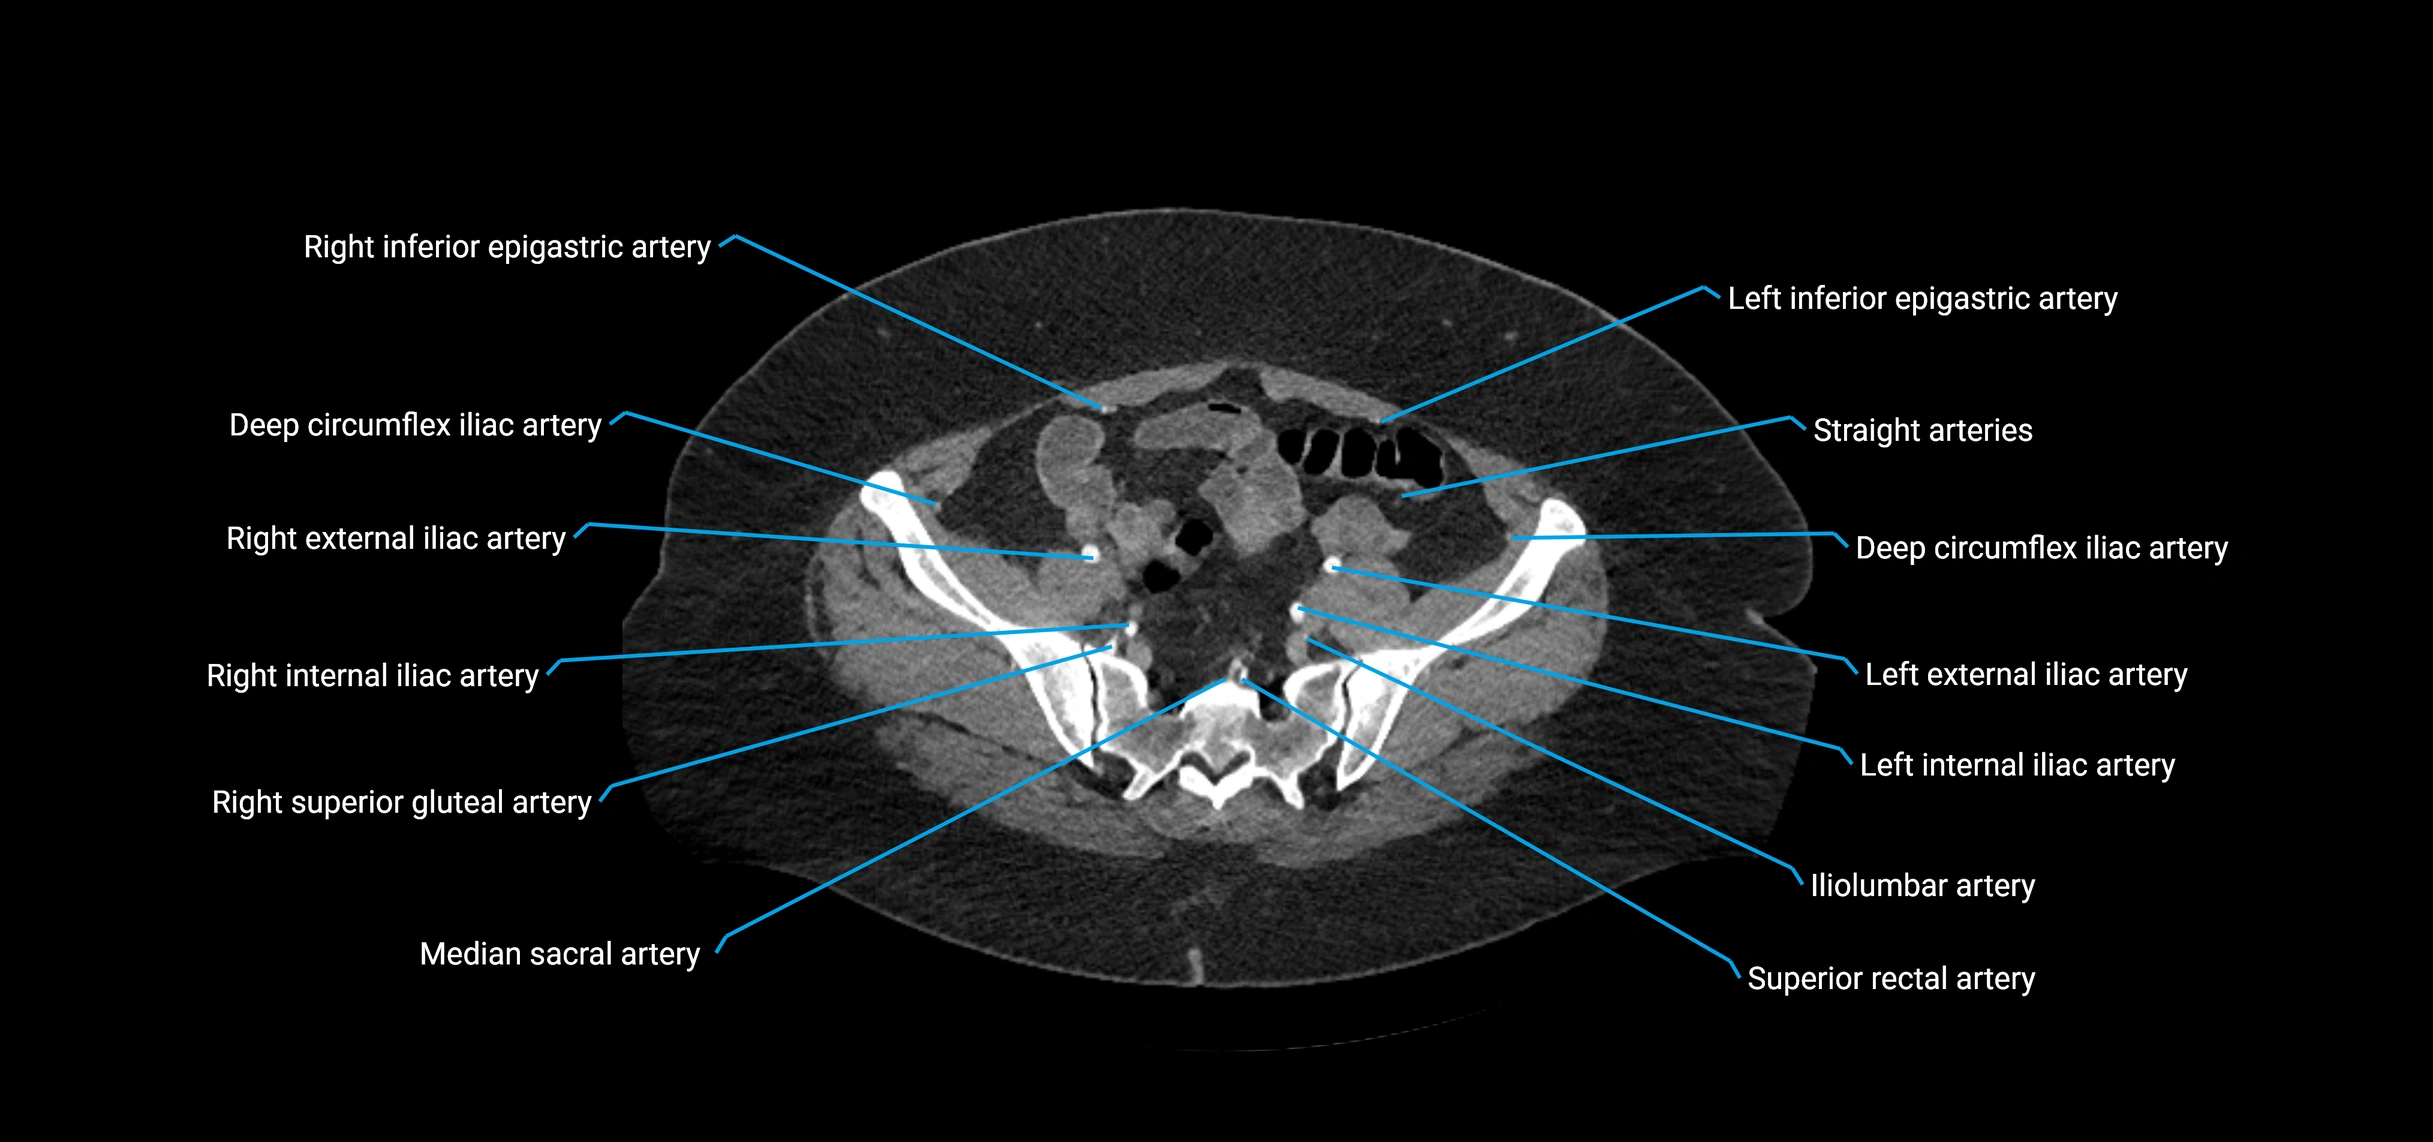

CT images

image

Contrast-enhanced CT (CTA):

• Gold standard for abdominal aortic imaging

• Provides excellent detail of lumen, wall, aneurysm, thrombus, and branch vessels

• Multiplanar and 3D reconstructions help in aneurysm measurement, stent graft planning, and dissection evaluation

• Parietal branches: inferior phrenic arteries, lumbar arteries, median sacral artery

• Terminal branches: right and left common iliac arteries